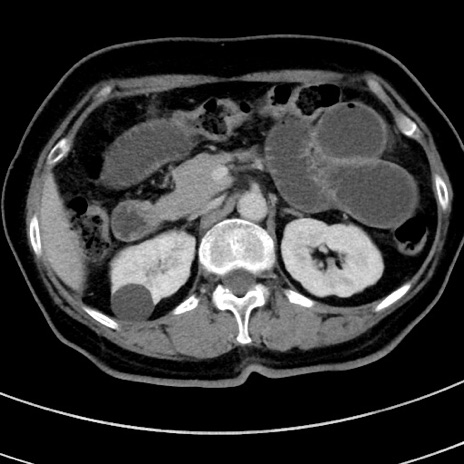

症例9(横断像)

【症例】 60歳代女性

【主訴】むかつき、みぞおちの痛み

【現病歴】3日前よりむかつきがあり、食事がとれない。

【既往歴】糖尿病

【身体所見】発熱なし、心窩部圧痛軽度あるも、腹膜刺激症状なし。

【データ】WBC 7400、CRP 1.92